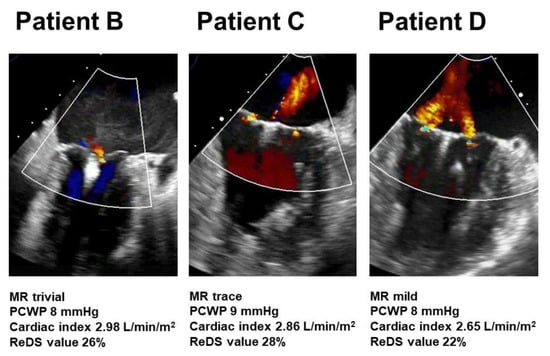

Patient A was medically managed without any complications. Other patients received MitraClip procedure 39 days, 12 days, and 8 days following testing without any complications. Transesophageal echocardiography images in patients B–D following MitraClip procedures are displayed in Figure 3. The degree of residual MR ranged between trivial and mild. Their hemodynamics data and ReDS values were within acceptable ranges. Of note, patient D showed mild residual MR but the ReDS value was only 22%.

Figure 3. Transesophageal echocardiography following MitraClip procedure in patients B–D. MR, mitral regurgitation; PCWP, pulmonary capillary wedge pressure; ReDS, remote dielectric sensing.